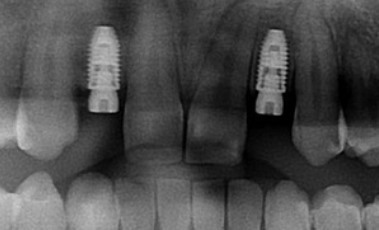

- Cas 5 : migration dentaire (d’origine fracturaire)

La racine de l’incisive centrale est fracturée et l’ancrage osseux s’est affaibli : la langue pousse la dent vers l’extérieur.

L’extraction implantation-immédiate avec une mise en esthétique immédiate donne au patient un confort et de l’esthétique pendant la période d’ostéointégration.

La couronne d’usage redonne un sourire satisfaisant à la patiente.